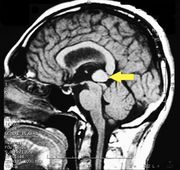

| 17:30, 26 February 2023 | Pineal cavernoma post surgery 1.jpeg (file) |  |

128 KB | 1 | |